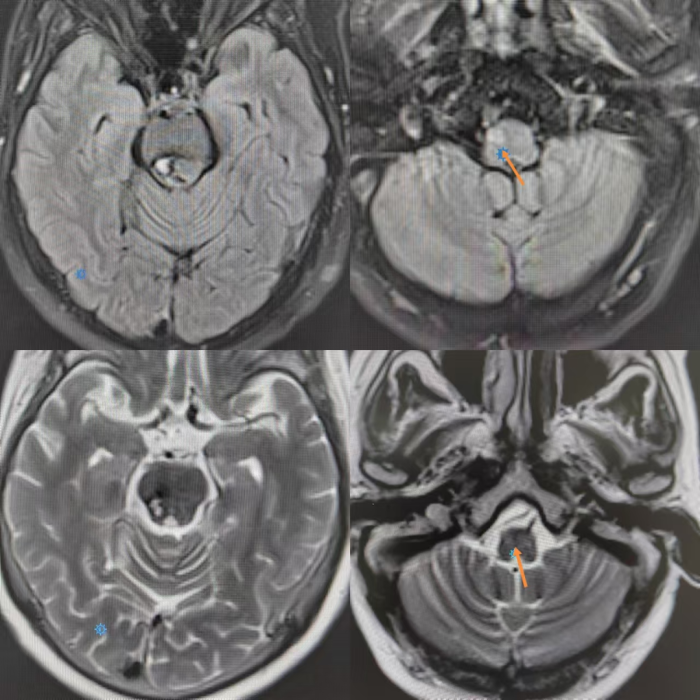

神经内科执行主任申向民教授详细询问患者病史,并为其进行全面的神经系统体格检查,仔细查阅患者既往头颅影像学表现,迅速组织团队为患者安排了头颅磁共振检查,结果显示——患者头颅右侧延髓下橄榄核区域出现肿胀,表现为T2和T2FLAIR高信号影,脑桥和中脑区域可见陈旧性出血改变。

8月1日,患者复查头颅磁共振结果显示,右侧延髓T2WI、FLAIR、DWI呈高信号,ADC呈稍高信号

8月1日,患者复查头颅磁共振结果显示,右侧脑桥T2WI及FLAIR中心高信号,周围低信号